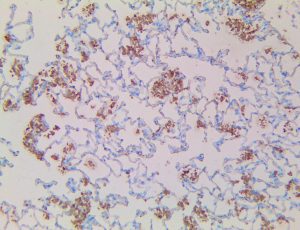

The first cytokines released are interleukin 1β (IL-1β) and tumor necrosis factor-α (TNF-α), which attract a variety of circulating white blood cells (WBCs) to the infection site, including neutrophils, monocytes, macrophages, and natural killer (NK) cells. This response, along with the antipathogenic chemicals released by these cells (i.e., complement), comprise the innate immune response. These cells directly attack the invading pathogen and also release additional cytokines, chief among them interleukin-1 and 6 (IL-6). IL-6 is essential for invoking the adaptive immune response, which calls T-cells, B-cells, and T helper (Th) cells to the infection site. IL-6 also stimulates further recruitment, proliferation and activation of macrophages.

This activation induces inflammatory monocytes to highly express IL-6, starting a localized and then systemic cascade effect that results in hyperproduction of IL-6, which accelerates the inflammatory process. Because IL-6 also increases vascular permeability, excessive levels cause blood vessels to become very leaky. This, along with clotting factors released from vascular endothelial cells, stimulates the coagulation cascade, resulting in microthrombosis (tiny clots), which leads to ischemia and tissue death of the kidney, intestines, heart, liver, brain and extremities.